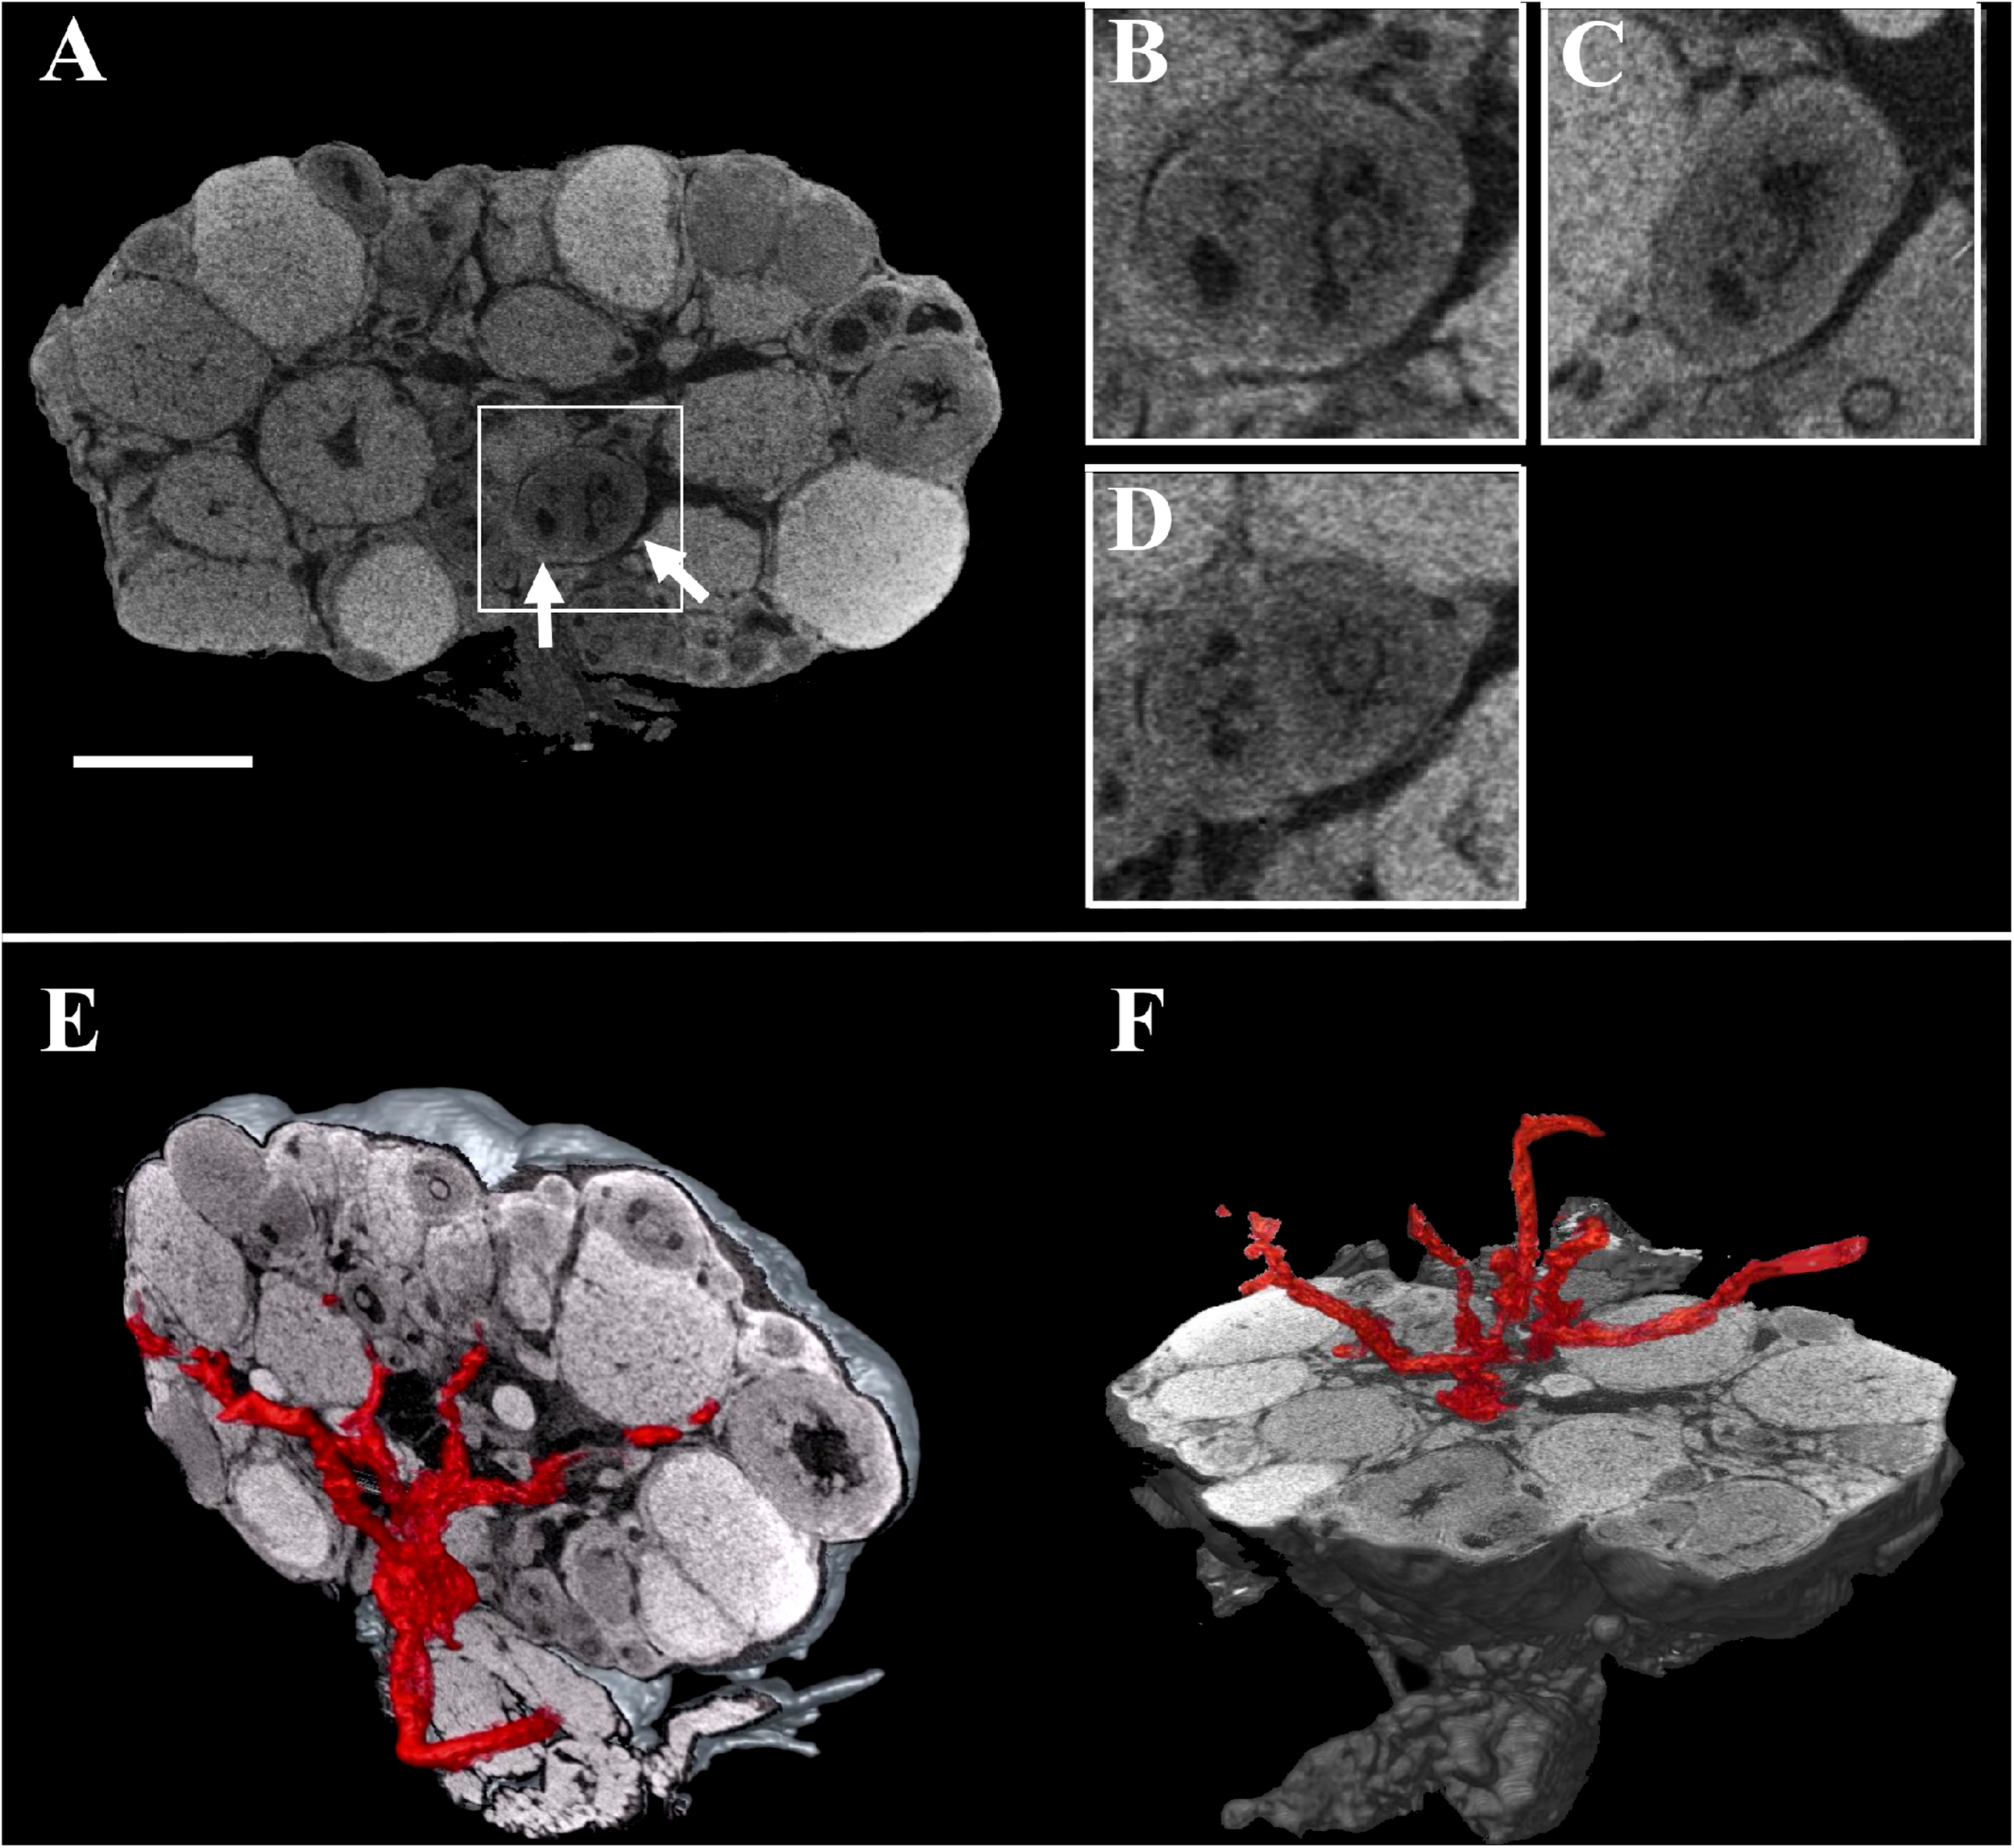

These digital microCT images were further analyzed to visualize each single follicle along the three orthogonal sections (Figures 2A–D) and to reconstruct, with a volume rendering software, a 3D model of the ovary which combined both follicular and vascular components (Figures 2E,F).

FIGURE 2

Combined three-dimensional rendering of microCT sections of the ovary and of the main vasculature. (A) A representative equatorial microCT slice. Inset, two T7 follicles (arrows). (B–D) coronal, sagittal, and axial planes of the two T7 follicles shown in the inset. (E,F) Reconstruction of the main vasculature on the coronal and axial section, respectively. Bar, 500 μm.